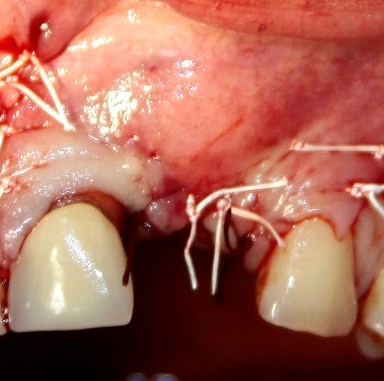

И швы:

Как и на первом этапе, мы делаем назначения и даем рекомендации, а также в течение нескольких дней контролируем состояние послеоперационной раны.

Вот так она выглядит через день после операции:

Разумеется, пациентку никто не оставляет без зуба. Если Вы обратили внимание, то заметили справа на правой фотографии остатки металлического ретейнера. С помощью него к соседним от дефекта зубам фиксируется адгезивная коронка. Она, конечно же, не дает возможности нормально кусаться, но зато отлично маскирует отсутствие зуба. Таким своеобразным временным протезированием пациентка пользуется от начала и до конца лечения.